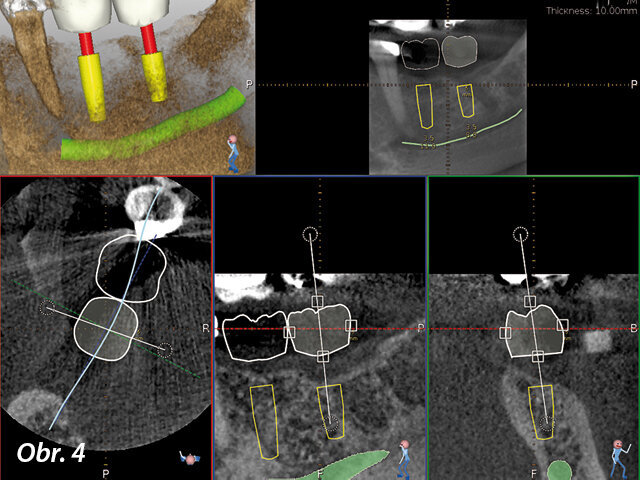

V našem případě byla tedy vytvořena šablona NaviStent s umístěním výchozího bodu a dva týdny před chirurgickým zákrokem byl pořízen CBCT sken (obr. 2). Plán ošetření byl vytvořen ihned po skenování (obr. 3) za přítomnosti pacienta. Mohl tak vidět navrhované ošetření zobrazené softwarem Navident a ocenit velkou péči věnovanou dosažení optimálního umístění implantátu s minimálním rizikem potenciálních komplikací (obr. 4). Pacient byl ohromen a uklidněn díky nejmodernější technologii.

Byl jsem schopen dosáhnout nejlepší bukální a lingvální pozice implantátů i jejich vzájemného vztahu a vztahu vůči sousedním zubům

Pacient mohl vidět navrhované ošetření zobrazené softwarem Navident

Plán ošetření byl vytvořen ihned po skenování

CBCT sken byl pořízen dva týdny před chirurgickým zákrokem